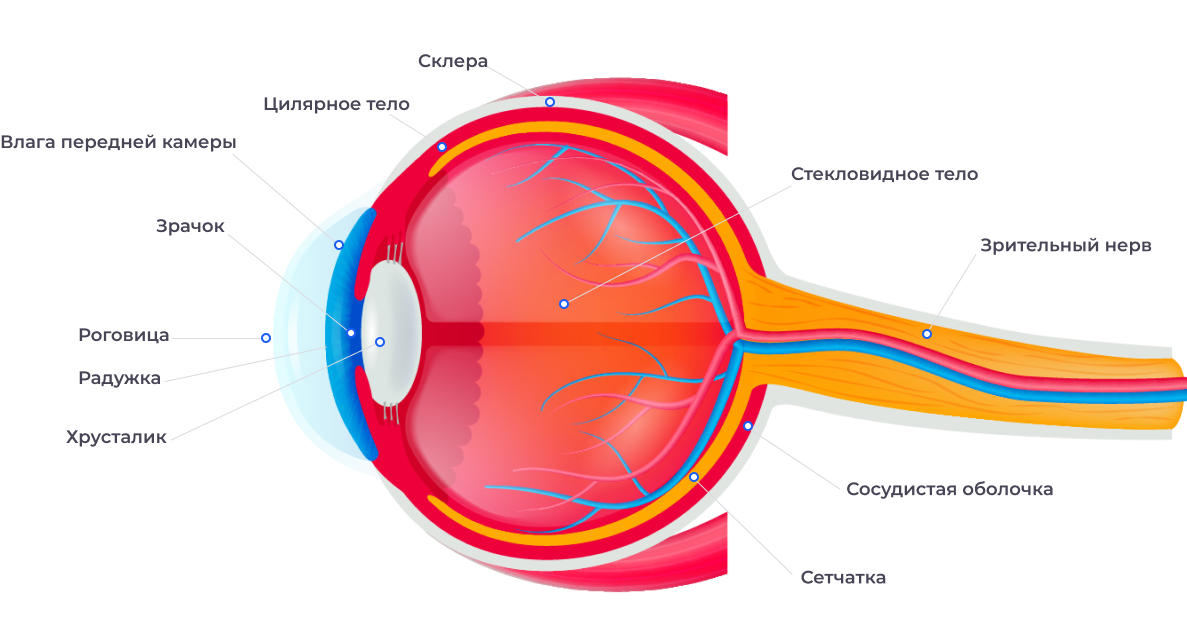

КТ-графики и изображение строения глаза